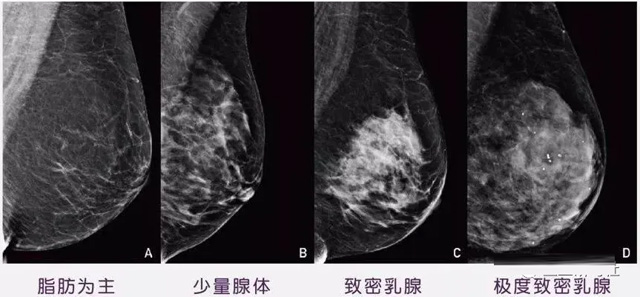

女性乳腺的自我檢查,特別是注意有小結(jié)節(jié),腫塊,乳頭有液體滲出情況,需要通過(guò)乳腺DR,X光線,磁共振等影像技術(shù)檢查。胸的大小跟乳腺癌沒(méi)多大關(guān)系,乳腺的密度大發(fā)病率高一些,胸小脂肪少致密性大。更容易乳腺癌。這個(gè)還不能通過(guò)自我檢查來(lái)確認(rèn)。致密乳腺組織看上去是白色或淺灰色需要通過(guò)乳腺X射線檢查。

乳腺X射線有輻射,40歲以下的女性沒(méi)有高危因素跟臨床特征,醫(yī)生都是不建議使用鉬靶檢查。乳腺超聲無(wú)創(chuàng)無(wú)輻射,對(duì)乳腺組織分辨率高。可以將乳腺腫塊從致密型乳腺組織中輕松查出來(lái),多普勒模式檢查乳腺及病變,超聲小于1厘米的病灶非腫塊性乳腺癌檢出率低。超聲檢查結(jié)果依賴醫(yī)生水平和經(jīng)驗(yàn),乳腺DR超聲推動(dòng)乳腺超聲圖像的標(biāo)準(zhǔn)化,提高檢查的準(zhǔn)確率。對(duì)乳腺組織內(nèi)的細(xì)小鈣化灶, 從范圍、乳腺X射線形態(tài)以及分布特點(diǎn)上進(jìn)行定性診斷。造影劑增強(qiáng)型乳腺X線攝影靜脈注射碘化造影劑結(jié)合乳房X線攝影。磁共振MRI對(duì)乳腺癌研究的深入對(duì)軟組織具有較高的分辨率等特點(diǎn),在臨床上被廣泛認(rèn)可。乳腺CT的探測(cè)器圍繞著乳房成像,無(wú)痛無(wú)擠壓,3D乳房圖像乳腺病灶的大小、數(shù)量、形狀、位置以及血管分布。一次掃描可創(chuàng)建多達(dá)兩千張投影圖像 。乳腺PET,適合普通人群和乳腺癌高危人群早期檢測(cè),發(fā)現(xiàn)極早期微小病灶并明確定性。